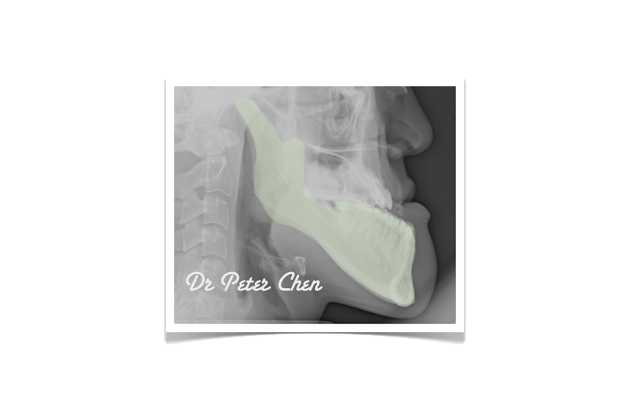

嚴重 戽斗

前陣子有個軍人來找我,主要的問題是下顎骨突出(戽斗)所造成的前牙開咬,只有後排幾顆牙齒碰得到。他吃東西非常不方便,也因此常被長官罵說怎麼吃東西這麼慢,因為不敢吃太久,體重一直過瘦。